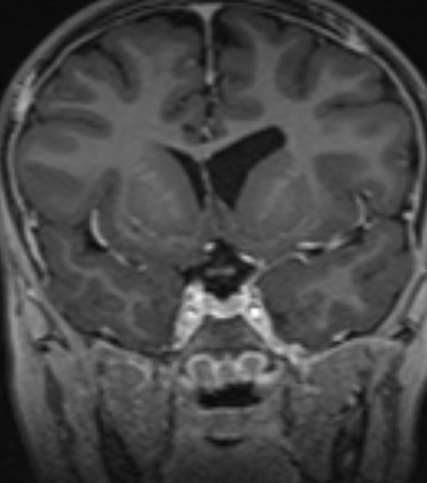

Please find below some images from the case:

OCT from early Jan 2026, when she first re-presented with vision loss in the left eye and disc edema. Very poor quality with poor fixation, but you can get a better sense of the left optic disc edema from the macular images.

Better quality OCT from the end of Jan after the shunt placement. The macular rasters don't catch the disc this time, so it's hard to compare, but I'd say the edema has clearly improved.

Post op MRI shows no significant change in the size of the ventricles, low lying cerebellar tonsils, similar to previous. Chiasm and nerves are small, unchanged from an MRI one year ago.